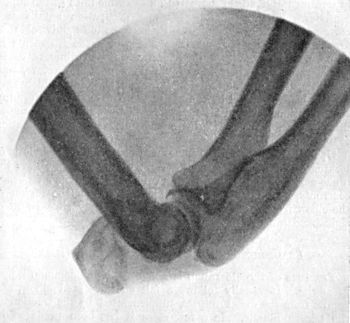

38.Radiogram of Incomplete Backward Dislocation of Elbow91

39.Forward Dislocation of Elbow, with Fracture of Olecranon93